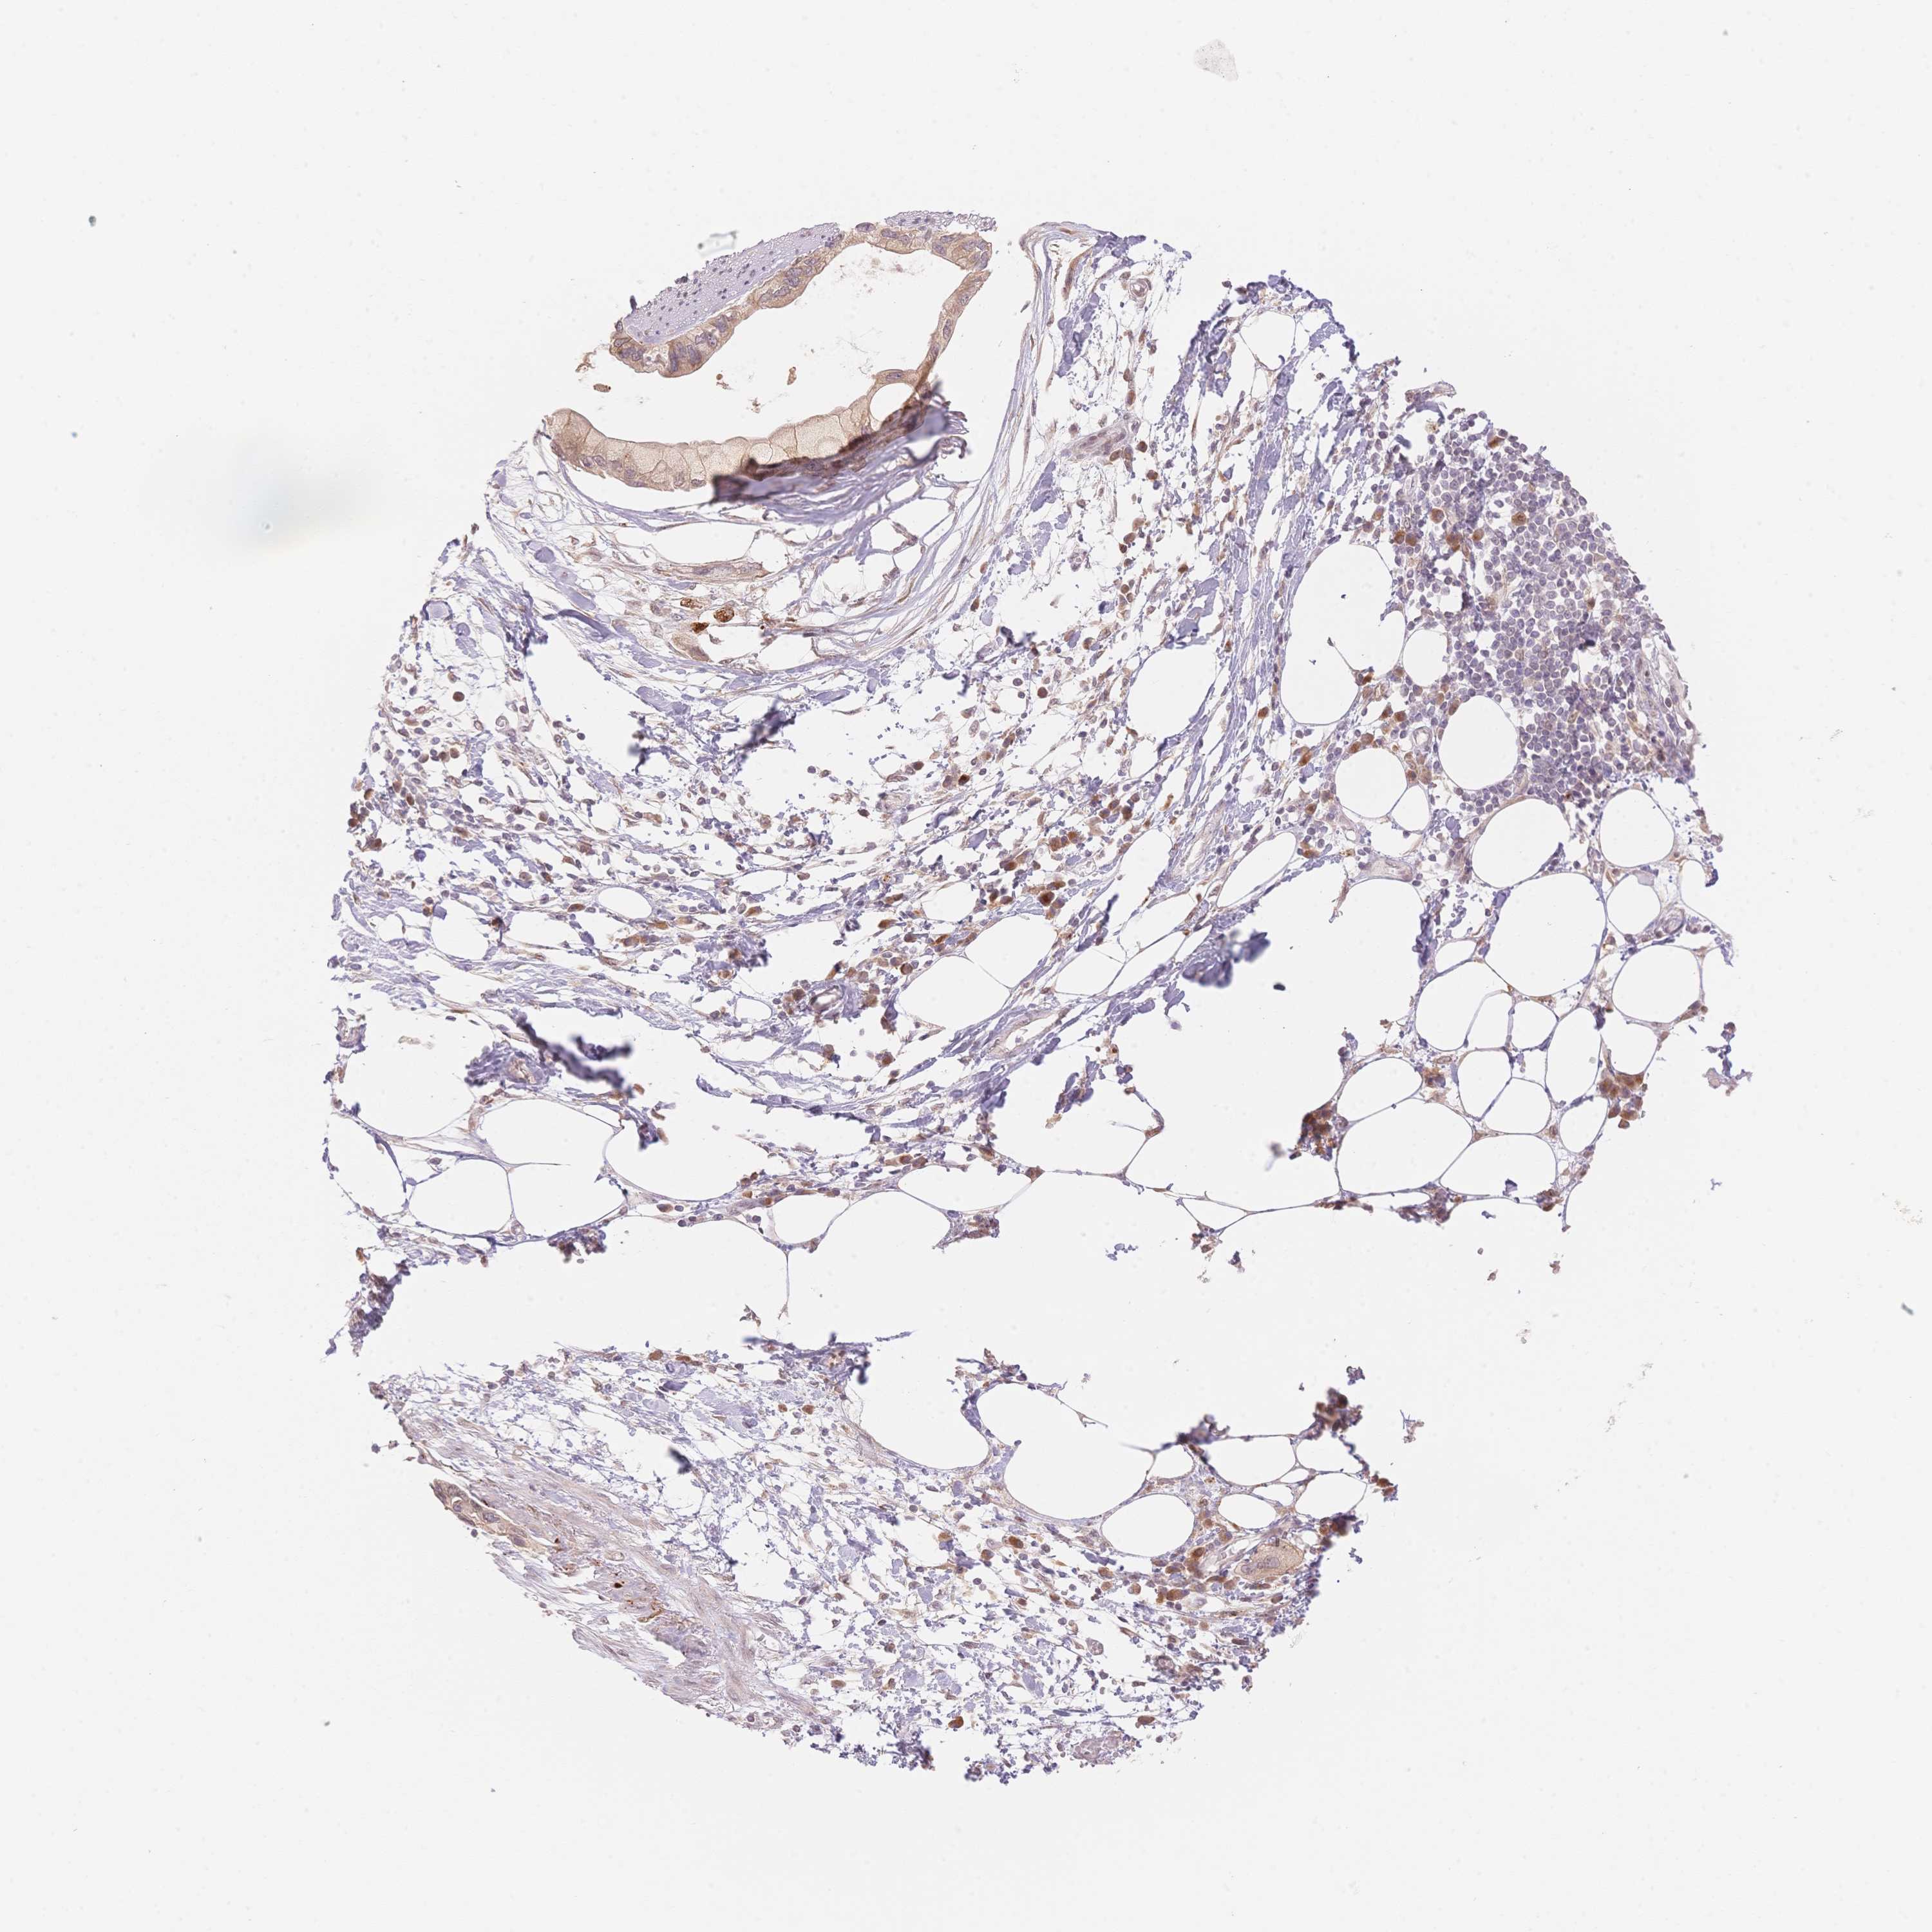

PANCREATIC CANCER - Protein expressioni

A mouse-over function shows sample information and annotation data. Click on an image to view it in a full screen mode. Samples can be filtered based on level of antibody staining by selecting one or several of the following categories: high, medium, low and not detected. The assay and annotation is described here.

Note that samples used for immunohistochemistry by the Human Protein Atlas do not correspond to samples in the TCGA dataset.

Antibody stainingi

Antibody staining in the annotated cell types in the current human tissue is reported as not detected, low, medium, or high, based on conventional immunohistochemistry profiling in selected tissues. This score is based on the combination of the staining intensity and fraction of stained cells.

Each image is clickable and will lead to virtual microscopy that enables deeper exploration of all samples and also displays staining intensity scores, fraction scores and subcellular localization as well as patient and tissue information for each sample.

Antibody HPA061803

Antibody HPA062802

Antibody CAB046022

Staining

High

Medium

Low

Not detected

Intensity

Strong

Moderate

Weak

Negative

Quantity

>75%

75%-25%

<25%

None

Location

Nuclear

Cytoplasmic/membranous

Cytoplasmic/membranous,nuclear

Adenocarcinoma, NOS